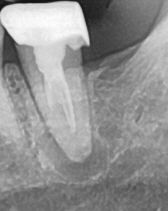

어금니뿌리염증치료관해서질문드려요

신경치료하고 금씌운이빨뿌리에 염증이생겼는데

사진으로 봐서는 뿌리끝에 큰 병소가 있는 것으로 보입니다. 이런 경우 치아 신경관 내부가 감염되었다면 재신경 치료를 해서 감염 물질을 제거해 줄 수 있습니다.

보철물을 한 상태에서도 신경 치료를 할 수 있지만 보철치를 한 치과가 아니라면 위험도를 감수하지 않고 싶어 할 수 있습니다. 일반적으로는 보철물을 제거하고 신경 치료를 하게 됩니다.

• 안녕하세요 치과의사 김철진입니다. 엑스레이 상으로 보면 치아 뿌리끝에 염증이 많은거 같습니다. 저 상태라면 사용할때까지 사용하시고 불편하시면 발치를 하시는게 좋을것같습니다.

• ct를 찍어거나 직접 재신경치료를 해보아야 알겠지만

신경치료가 어려운 형태의 치아 일 가능성이 높습니다.

개인적소견으로는 재신경치료를 해도 성공률이 낮아보이며, 발치, 골이식 후 임플란트 하시는게 좋아 보이십니다.

1. 재평가와 상관없이 어차피 재신경치료를 하려면 금 크라운은 뜯어내야 합니다. 지금으로서는 방사선 사진 상 염증이 명확히 보여 평가 자체를 하기 위해서는 크라운을 뜯을 필요는 없습니다.

2. 언급한 것 외 치료방법으로는 치근단절제술을 고려해볼 수 있으나 현미경 등의 장비가 필요하고, 대학병원 보존과에서 주로 하는 술식입니다.